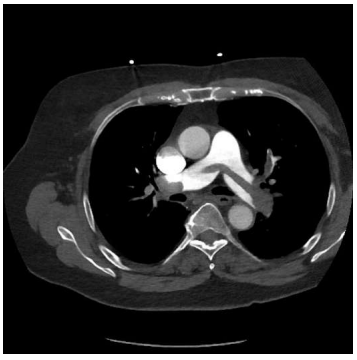

Um homem de 62 anos de idade, com câncer de pâncreas

metastático, apresentou-se com dispneia, dor torácica

ventilatório dependente e palpitações. Na admissão,

detectou-se que o paciente era hipotenso, taquicardíaco e

que estava com queda de saturação. Exames apontaram: PA

83x62 mmHg; FC de 128 bpm; ECG em ritmo de fibrilação

atrial; pocus com sinal de McConnell; e veia cava túrgida. A

angio TC de tórax está disposta na imagem a seguir.

Provas

Caso clínico hipotético para a questão.

Um homem de 62 anos de idade, com câncer de pâncreas

metastático, apresentou-se com dispneia, dor torácica

ventilatório dependente e palpitações. Na admissão,

detectou-se que o paciente era hipotenso, taquicardíaco e

que estava com queda de saturação. Exames apontaram: PA

83x62 mmHg; FC de 128 bpm; ECG em ritmo de fibrilação

atrial; pocus com sinal de McConnell; e veia cava túrgida. A

angio TC de tórax está disposta na imagem a seguir.